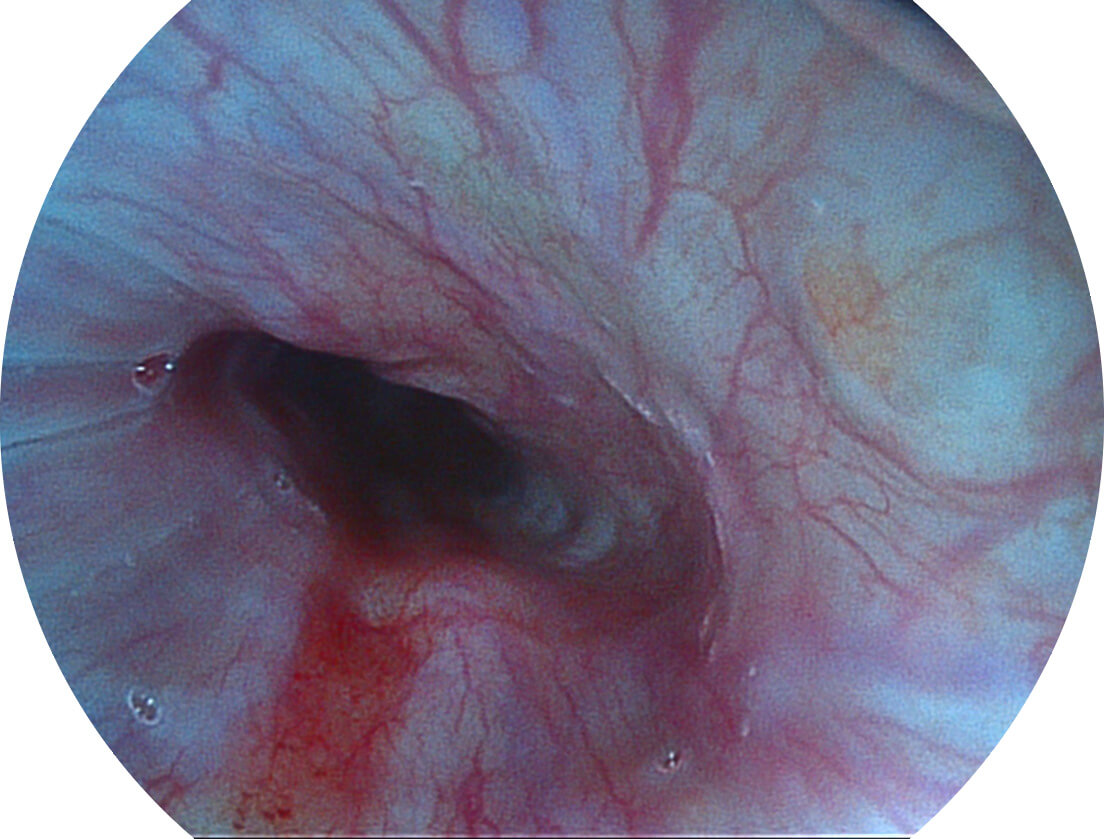

图像具有高亮度、高黏膜血管颜色对比度的特点,且不改变粘液、食物残渣、粪便的基本颜色,可在中远景下进行观察,助力消化道早期疾病的诊断。

采用光路合束技术,光谱自由度高,实现了更丰富的照明模式,染色模式SFI及VIST,从远景到近景,助力消化道早期疾病诊断。